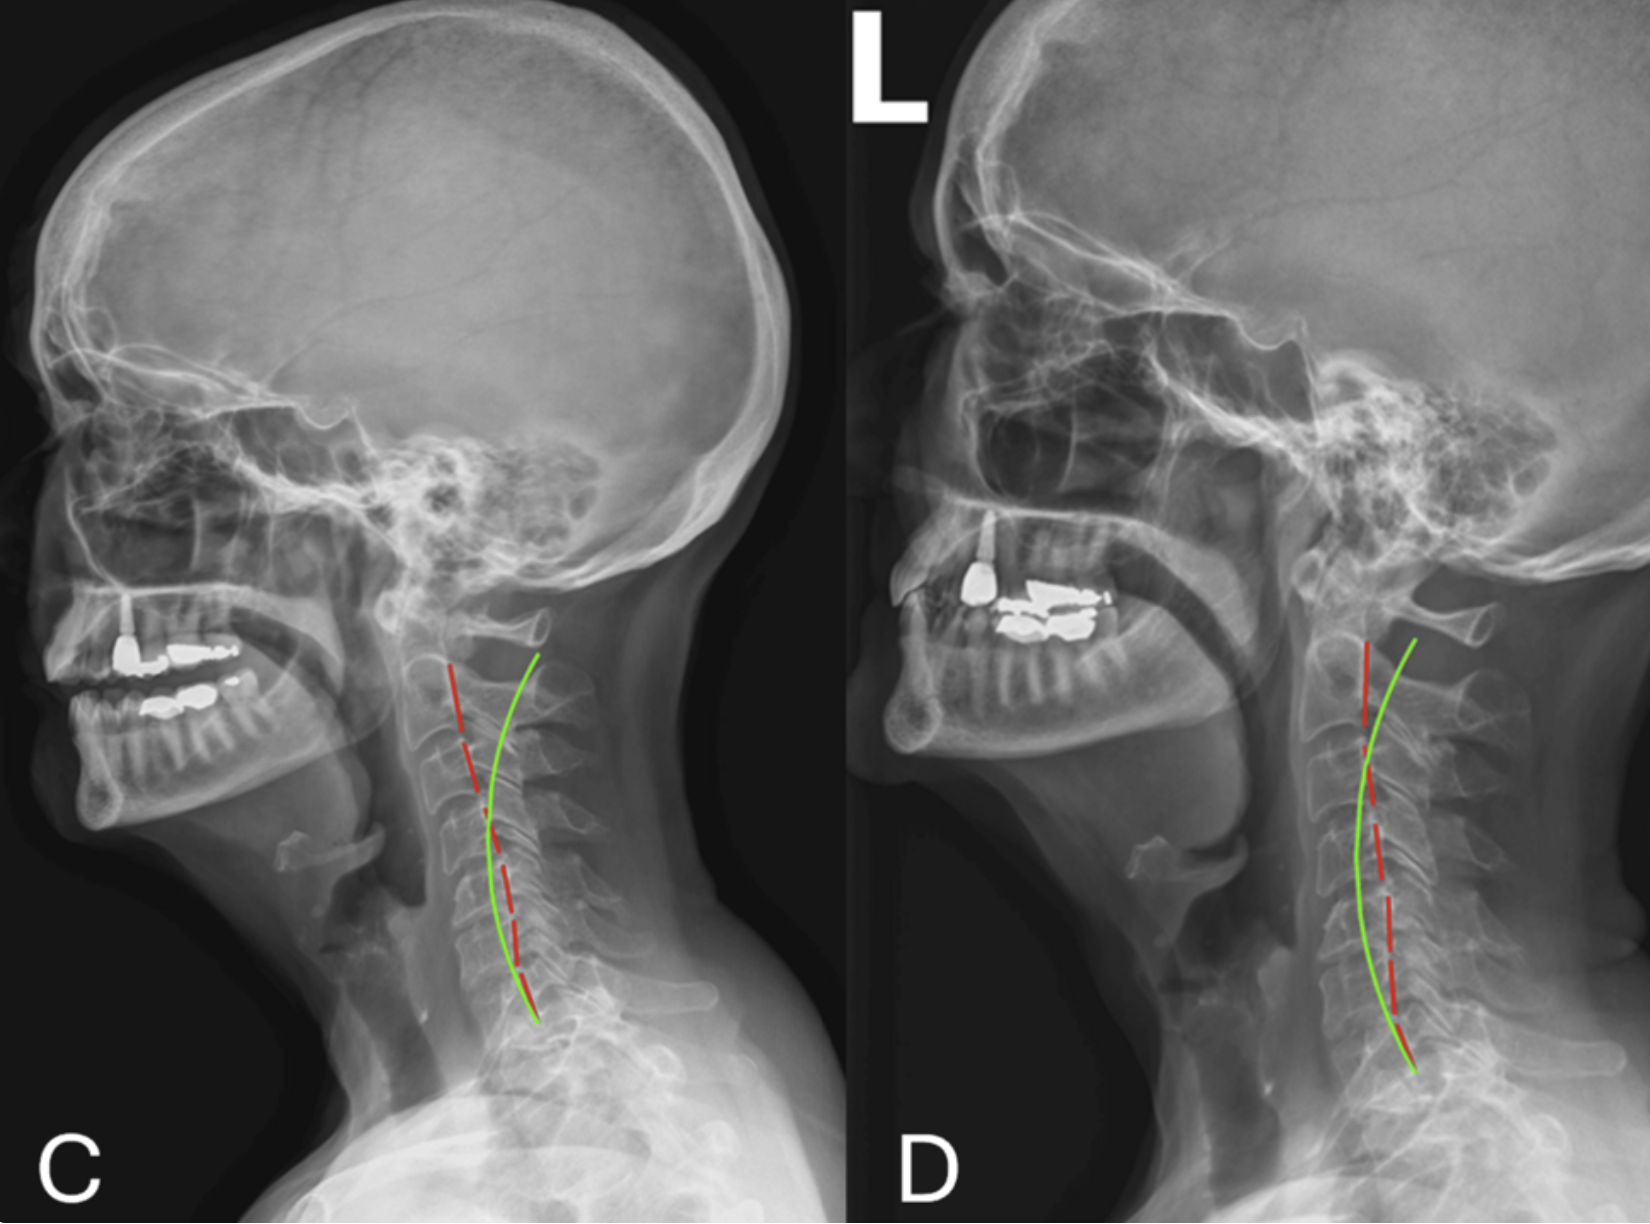

A scoliotic curve doesn't remain confined to one region of the spine. Instead, it creates a cascade of compensatory changes throughout the entire kinetic chain—the integrated system of the cervical spine, thoracic spine, lumbar spine, pelvis, and lower extremities working together to maintain balance and function. Over decades, these compensations accumulate and become maladaptive, contributing to chronic pain and dysfunction in areas both adjacent to and distant from the primary scoliotic deformity. New peer-reviewed research demonstrates that addressing kinetic chain dysfunction through non-surgical rehabilitation can yield significant clinical improvement in geriatric scoliosis patients.

The kinetic chain approach to geriatric scoliosis represents a paradigm shift in how we understand and treat this complex condition. Rather than attributing all pain and dysfunction to the primary scoliotic curve, this framework recognizes that decades of compensatory loading have altered spinal alignment and function throughout the entire kinetic chain. By comprehensively addressing these compensations and restoring global spinal alignment, non-surgical rehabilitation can deliver meaningful clinical improvement. The research is clear: older adults with scoliosis have more treatment options than they may have been told.

Whelan J P, Dick J M (March 25, 2026) Radiographic Sagittal Alignment and Kinetic Chain Alterations in Geriatric Patients With Scoliosis: A Case Series. Cureus 18(3): e105827. doi:10.7759/cureus.105827 Pubmed